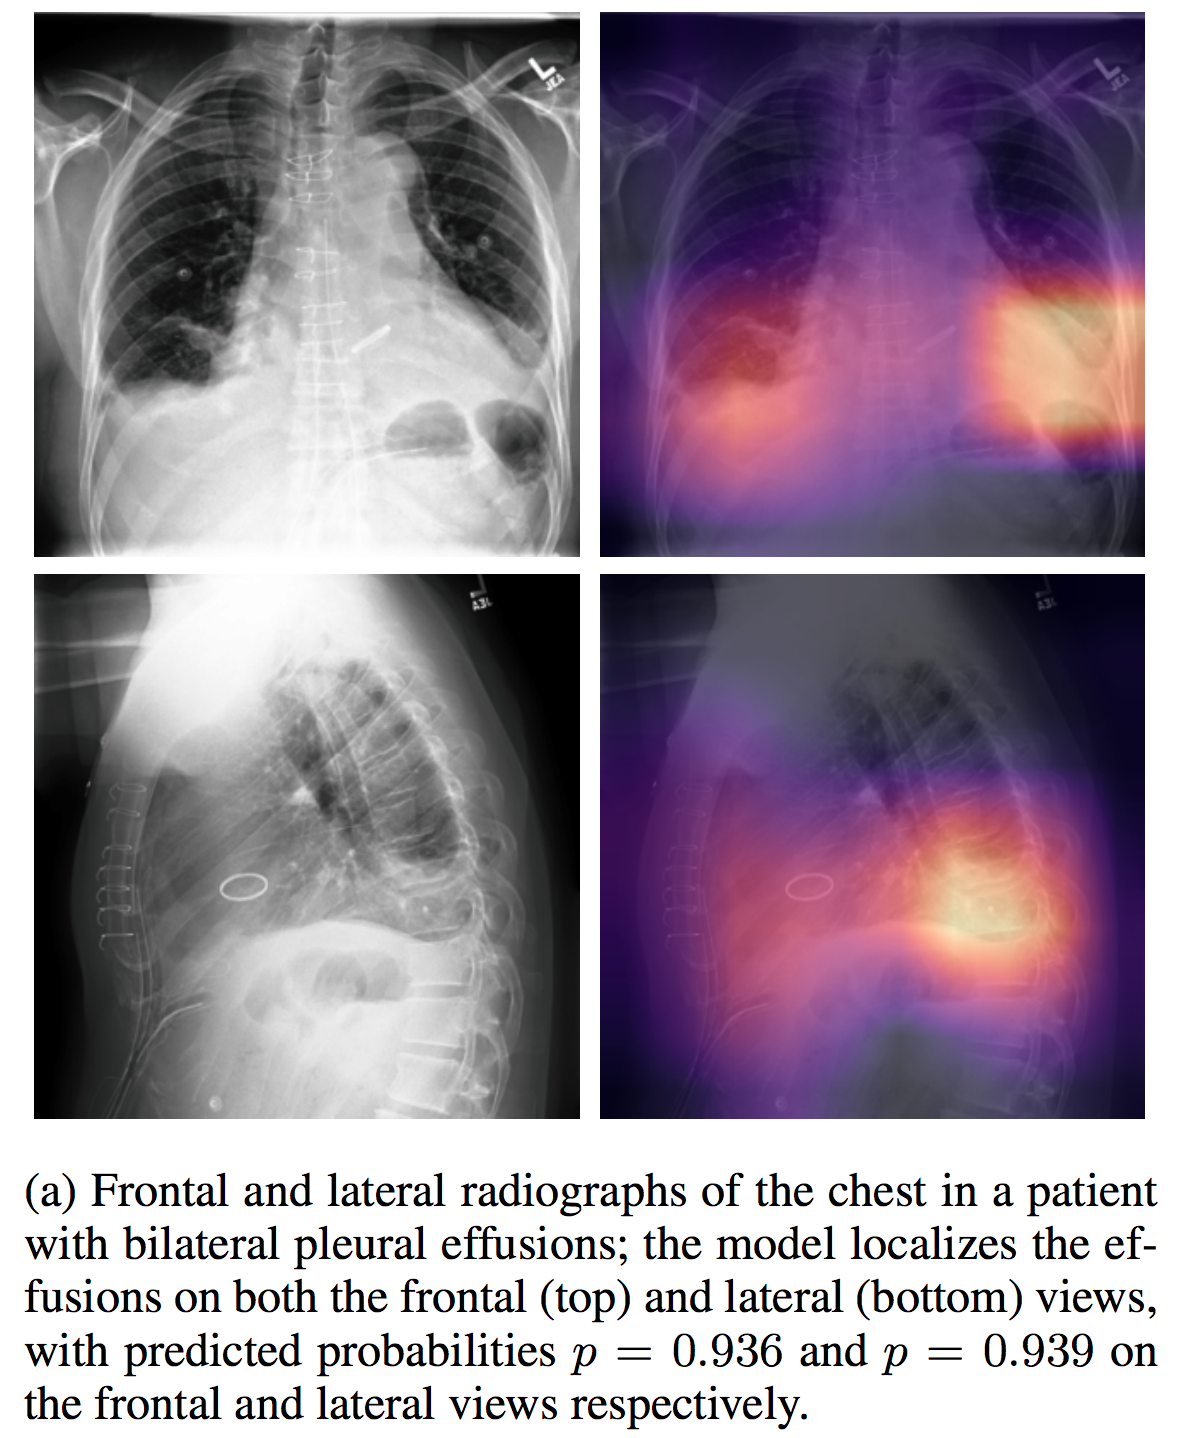

NIHChest Xray

| 名称 | 标注内容 | 类型 | 模态 | 数量 | 标签格式 | 文件格式 | License |

|---|---|---|---|---|---|---|---|

| NIHChest Xray | 14种肺部疾病/部分病灶位置 | 分类/检测 | CXR | 112,120 | csv | png | CC0: Public Domain |

介绍论文: ChestX-ray8: Hospital-scale Chest X-ray Database and Benchmarks on Weakly-Supervised Classification and Localization of Common Thorax Diseases